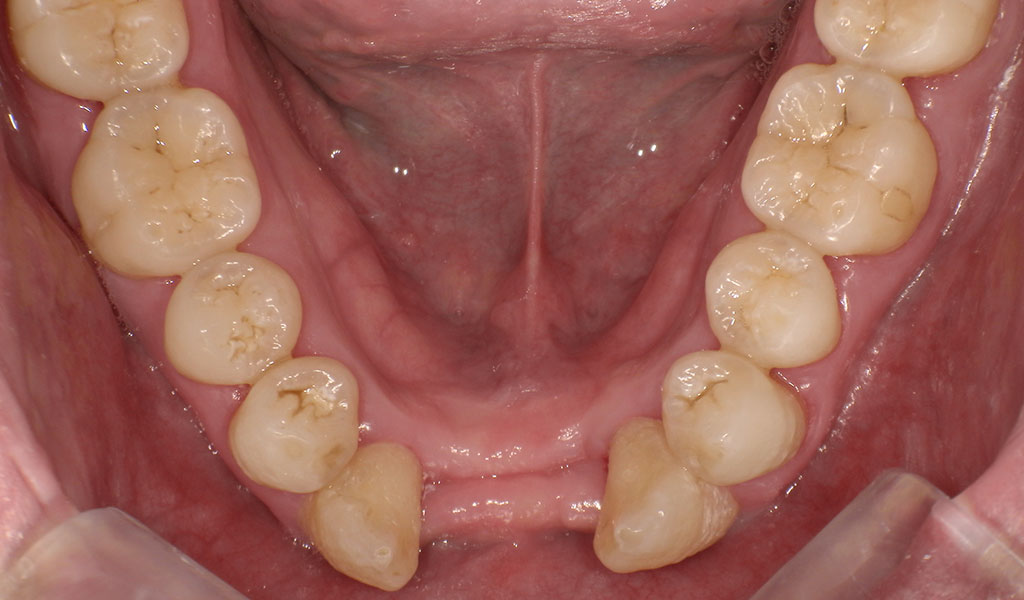

Before2(抜歯後)

ぐらつきの多い前歯下右2番、左1,2番を抜歯。

インプラントを入れるスペースが2本分しかないため、

通常手術にて、前歯下左右1番の骨にインプラントを埋め込みました。